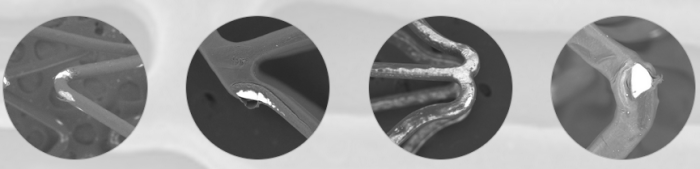

From crimping through delivery through calcified lesions, expansion and drug elution, drug-eluting stents endure substantial mechanical and chemical stress. Inherently brittle, traditional polymer coatings of drug eluting stents have been shown to develop surface imperfections and deformations, which under stress can crack and even peel away from the stent • Such cracking and peeling can lead to uneven drug release that may result in under- and over-dosing of the vessel wall. Moreover, they were associated with inflammation and thrombogenicity

- EluNIR’s elastomeric coating and coating process ensure an exceptional surface quality and long term coating integrity compared to pro-inflammatory cracking and peeling of durable polymers

- The first stent manufacturer to offer elastomer-based coating, Medinol eliminates the risks associated with cracking and peeling, delivering a smooth elastic surface

- EluNIR’s surface elasticity and smoothness is enabled by QualitySurface™ – our proprietary manufacturing technology that enables a high quality coating of stent panels with an elastomer and limus drug